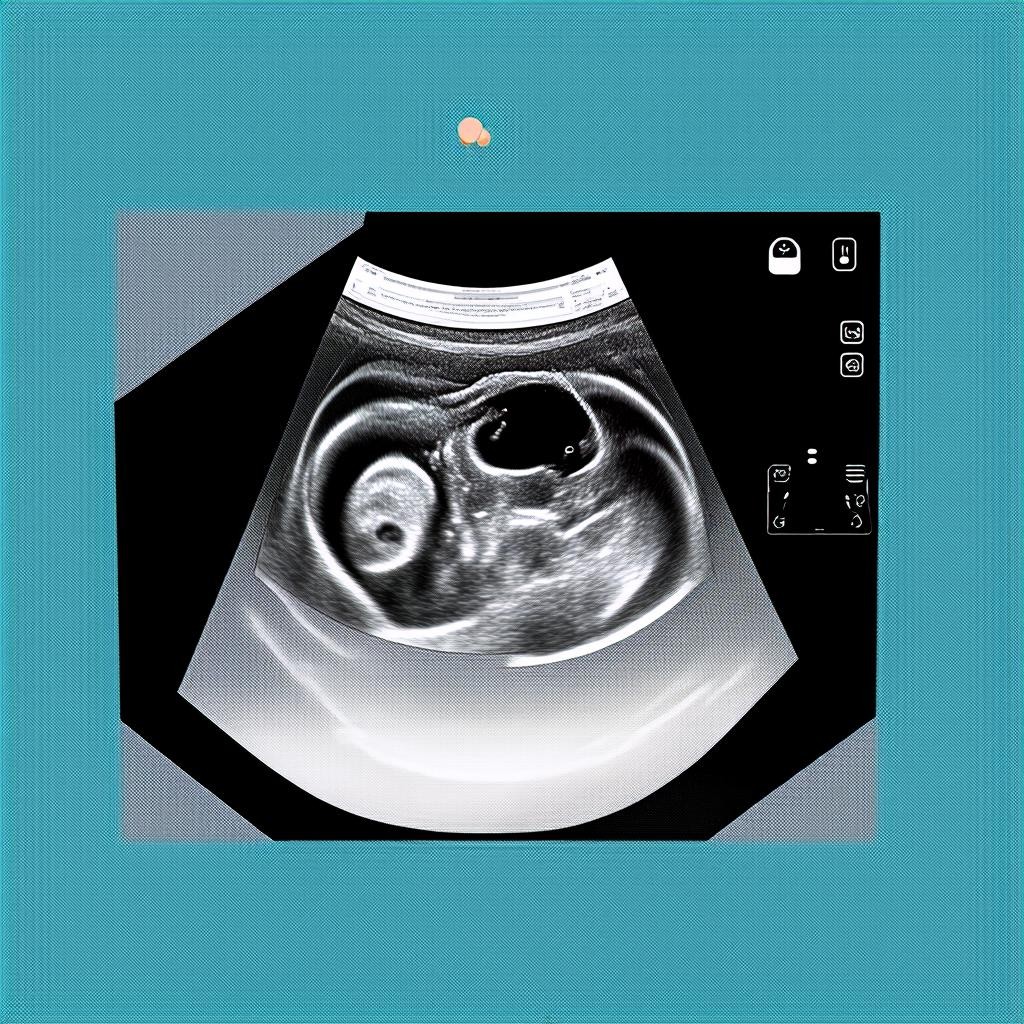

Что видно на УЗИ в 10 недель

На этом сроке эмбрион уже имеет явные человеческие черты. Вот что можно увидеть во время исследования:

- Размер плода: около 3-4 см, вес — примерно 5 грамм.

- Сердцебиение: норма — 140-170 ударов в минуту.

- Формирующиеся органы: ручки, ножки, голова, зачатки глаз, ушей и носа.

- Активные движения: плод уже может шевелиться, хотя мама этого ещё не чувствует.